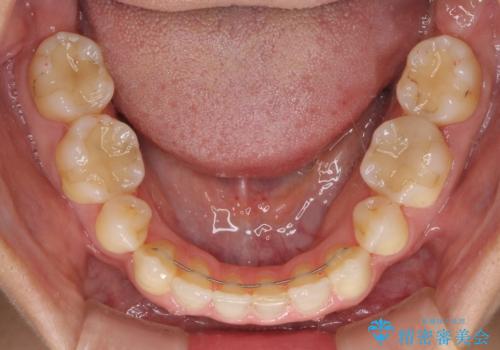

- 以前の矯正治療の後戻りにより、上の前歯にスペースができたことを気にして来院された患者様です。

インビザラインを用いて前歯のスペースを閉じつつ、上下の咬み合わせを構築していくこととしました。

隙間の空いてしまった前歯は、矯正治療で治療を行っても後戻りが起こりやすい傾向にあります。

マウスピースの保定装置をしっかりと装着しても空いてしまうため、細いワイヤーによる保定を併用することで後戻りを防止しています。